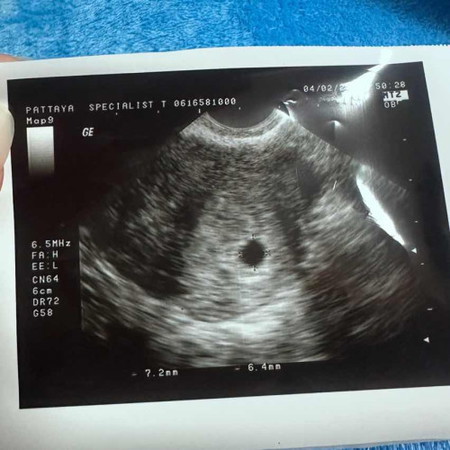

ถุงตั้งครรภ์ 5w

ไปอัลตราซาวด์ล่าสุด 5w ถ้านับจากประจำเดือนล่าสุด คุณหมอบอกถุงตั้งครรภ์เล็กมาก ไม่น่าใช่5w ตอน5w ถุงแม่ๆมีขนาดเท่าไหร่คะ เจอน้องตอนกี่wคะ

อันตร้าซาวด์5w เหมือนกันแต่เล็กมาก กว่าจะหาถุงตั้งครรภ์เจอ ถุงตั้งครรภ์ขนาด0.2เอง

ตอนไปซาวคุณหมอบอก 5 week แต่ถ้านับตามประจำเดือนวันแรกครั้งสุดท้าย 7 week ค่ะ

5w 5d ค่ะ เจอแต่ถุง ไม่เห็นไข่แดงไม่เห็นตัวน้องเลยค่ะ รอลุ้นต่อไป🙂

เจอถุงตอน 5weeks เหมือนกันค่ะ แม่อ้วนนิดหน่อย เห็นเป็นกลมๆค่ะ

บ้านนี้5w6d เจอถุง+ไข่แดง ได้ยินเสียงหัวใจด้วย

ซาวด์ตอน 5 w หมอบอกเจอถุงตั้งครรภ์ 1 cm. ค่ะ

เจอตอน 4 week ซาวแบบช่องคลอดนะคะ

เจอแต่ถุงเหมือนกันค่ะ 5w 3 d